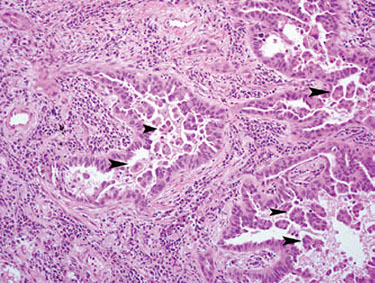

UIP

UIP/IPF - white tissue is interstitial fibrosis

UIP with patchwork distribution of fibrosis, fibroblastic foci (upper left), and honeycomb pattern (lower right)`